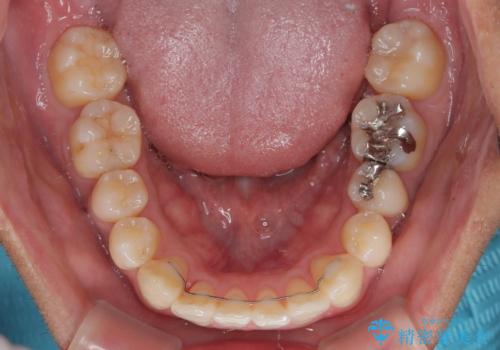

- 前歯のデコボコと右上の八重歯を気にして来院された患者様です。

マウスピース矯正とワイヤー矯正で悩んでいらっしゃいましたが、非常に強い咬合力であることや、お仕事柄不規則な生活リズムになることが多いとのことで、ワイヤー装置にて矯正治療を行うこととしました。

1年強でワイヤー装置を外すことができ、思ったよりも短期間で終了したため、患者様には大変喜んでいただきました。